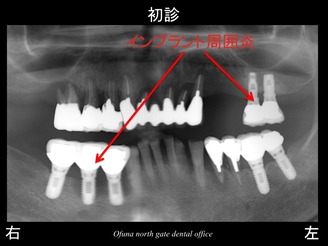

以下が初診時のレントゲンです。

初診時には、上顎前歯部が指でとれそうなくらい グラグラでした。

インプラント自体も出血、腫れがありインプラント周囲炎(インプラントの歯周病) になっていました。

上顎の天然歯は、骨吸収が非常に大きいため、グラグラしてました。

前の歯科医院では、天然歯の歯周病治療をまったく行わない状態で、インプラントを埋入したのです。